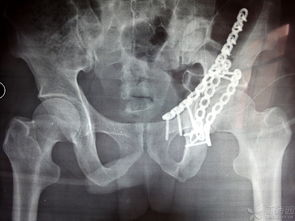

髖臼骨折股骨頭向后脫位,術(shù)后六個月了,